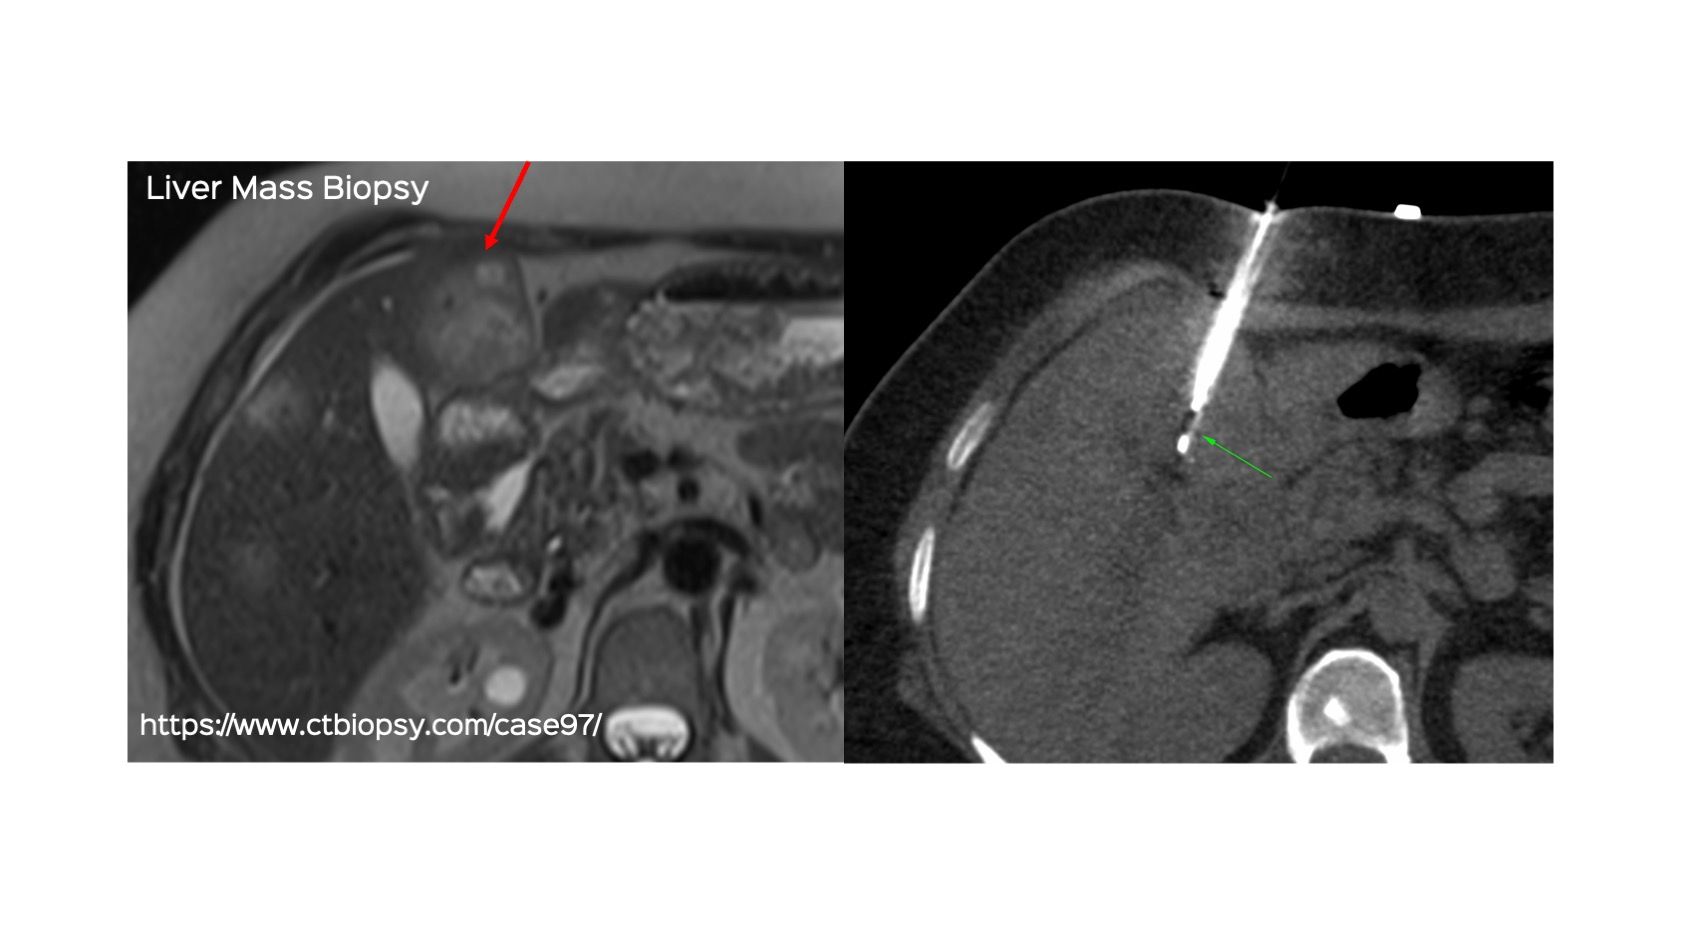

Case 97: Liver Mass Biopsy

Bhavin Jankharia - 11 July 2022